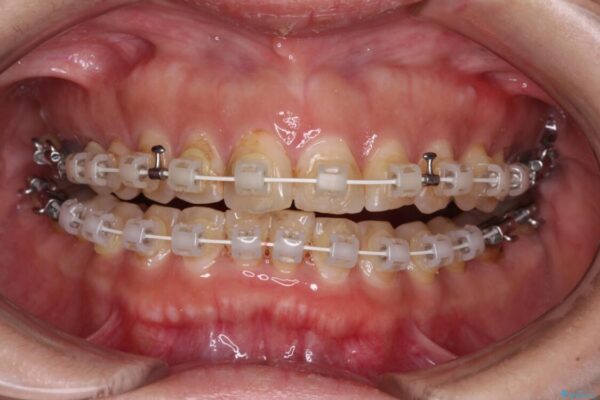

なるべく早めに治療を終えたいとのことで、補助装置を用いて上顎臼歯を後方に移動させ、同時にワイヤー装置にて整えることとしました。

舌の突出癖が原因で上下の歯に大きなスペースが生じていたため、舌のトレーニングをしっかり行っていただくことで、上顎歯列をスムーズに移動させることができました。

治療途中

• 【モニター】飛び出た前歯を整えたい ワイヤー矯正治療 治療途中画像